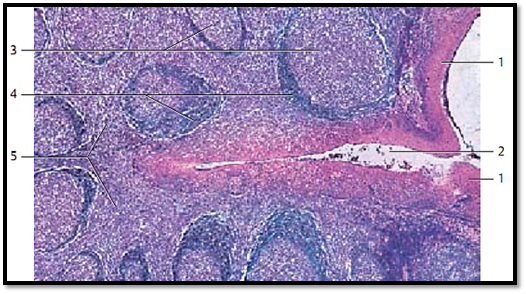

Palatine Tonsil

Longitudinal section of a crypt from the palatine tonsil with the adjacent layer of lymphoreticular tissue, which is part of the lamina propria of the mucous membrane. The multilayered nonkeratinizing squamous epithelium 1 at the mouth of the crypt and the tonsillar surface shows hardly any lymphocytes. Only in the depth of the crypt 2 is the squamous epithelium infiltrated by lymphocytes. Consequently, the epithelium there is more loosely organized and the structural integrity of the epithelium diminished. The germinal centers 3 display an incomplete layer that looks like a cap 4 with the top directed toward the crypt. This layer consists of small lymphocytes (B-lymphocytes). The T-cell region is locate d in the interfollicular zone 5 .

1 Multilayered nonkeratinizing squamous epithelium from the oral mucous membranes

2 Crypt

3 Germinal center

4 Follicle cap (B-lymphocyte cap) 5 Inter follicular areas

Stain: alum hematoxylin-eosin; magnification: × 12